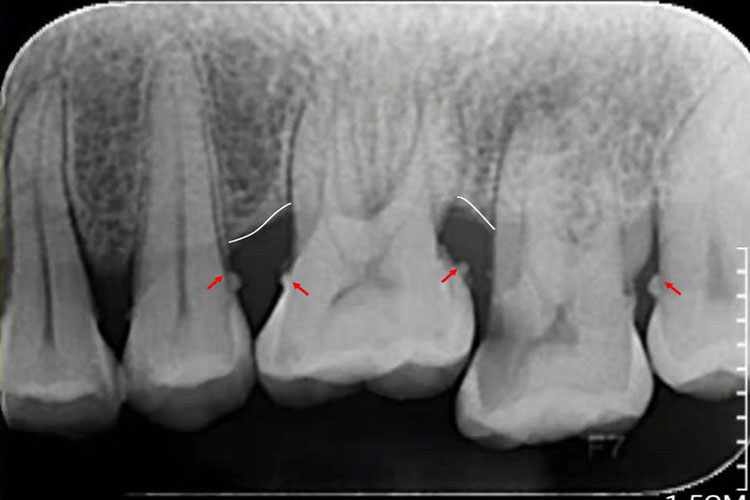

这种牙结石位于龈缘以下的牙面上,肉眼不可看到,可在X线上观察到,或需要探针探到。龈下牙石一般颜色较深,呈褐色或黑色,体积较小,质地较坚硬,与牙根表面的附着也较龈上牙石更牢固。龈下牙结石在任何牙位上都可形成,但以牙齿邻面和舌侧面较多。